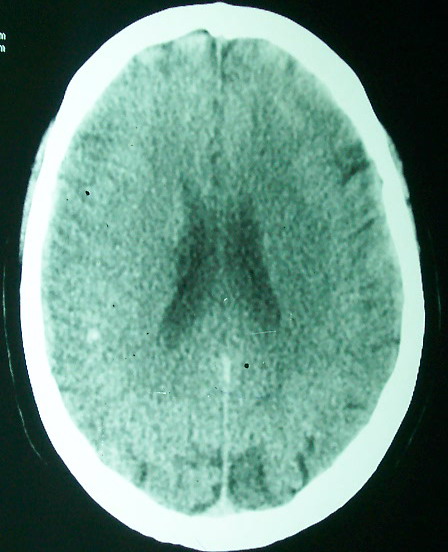

标题: CT18022:颅内多发稍高密度影

f     60    左侧肢体活动无力3天余,    神志情,  无抽搐史   无发热   否认囊虫接触史

有囊有节有钙化,这个表现符合混合型脑囊虫病.请结合临床资料并进行补体结合试验.

有囊有节有钙化,考虑混合型脑囊虫病.